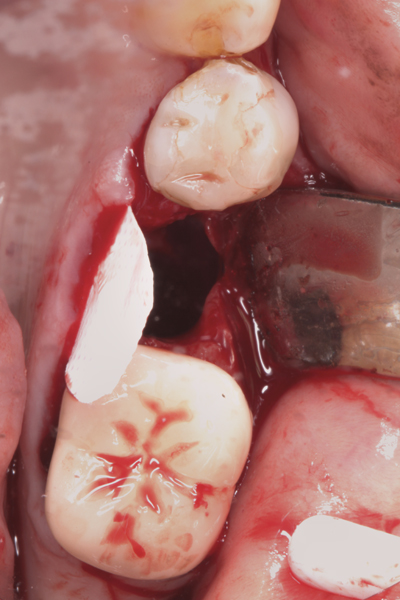

Fig 1. (Case 1) Tooth No. 19 manifested a buccal fistulous tract. Probing depth on the buccal was 8 mm.

Figure 1

Fig 2. Buccal flap elevated exposing buccal plate defect.

Figure 2